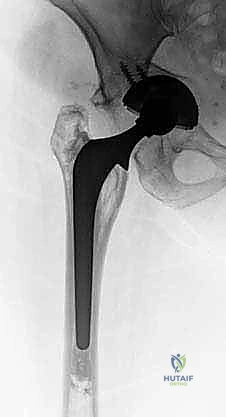

ما هو القفص المضاد للبروز (Antiprotrusio Cage)؟

القفص المضاد للبروز هو ابتكار هندسي طبي رائع، صُمم خصيصاً للتعامل مع الكوارث العظمية في الحوض. يتكون القفص عادة من التيتانيوم المرن أو الفولاذ المقاوم للصدأ عالي الجودة.

كيف يعمل القفص؟ (الميكانيكا الحيوية)

الفكرة الأساسية للقفص هي "تجاوز العيب العظمي" (Bridging the defect). بدلاً من محاولة تثبيت المفصل الجديد في العظم المتآكل والضعيف في المركز، يمتلك القفص "أجنحة" أو حواف تمتد لتتصل بالعظام السليمة والقوية المحيطة بالحُق:

1. الشفة العلوية (Iliac Flange): تمتد لأعلى لتُثبت بمسامير قوية في عظم الحرقفة (Ilium) الصلب.

2. الشفة السفلية (Ischial Flange): تمتد لأسفل لتُغرس أو تُثبت في عظم الورك (Ischium).

بهذه الطريقة، عندما يقف المريض، لا ينتقل وزنه إلى العظم الضعيف المحطم، بل ينتقل عبر هيكل القفص المعدني الصلب إلى العظام السليمة في الأعلى والأسفل. هذا يحمي الترقيع العظمي (الذي يتم وضعه تحت القفص) من الضغط المفرط، مما يسمح له بالالتئام والتحول إلى عظم حي قوي بمرور الوقت. بمجرد تثبيت القفص بقوة، يتم تثبيت كوب بلاستيكي (Polyethylene Cup) داخله باستخدام الأسمنت الطبي، ليتمفصل مع رأس عظم الفخذ الجديد.